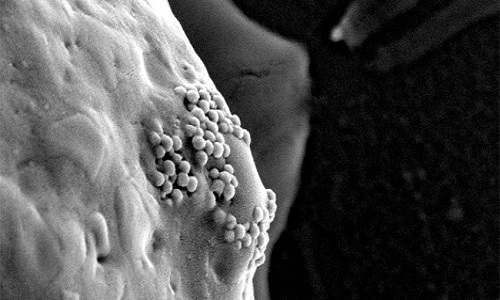

| Các hạt nano vàng bám trên bề mặt tế bào ung thư (Ảnh: D. S. Wagner) |

Những hạt nano vàng có xu hướng thấm qua các lỗ mạch và tập trung xung quanh khối u khi chúng được tiêm vào mạch máu cơ thể người bệnh. Khi các tế bào ung thư phát triển chúng sẽ bao phủ các hạt nano vàng này. Sau khi lọt vào bên trong tế bào ung thư, các hạt nano này sẽ được nung nóng bằng tia laser hồng ngoại hoặc sóng điện từ và đốt cháy các tế bào ung thư, tiêu diệt chúng.

Nhóm nghiên cứu cũng đã tiến hành gắn hạt nano vàng vào các kháng thể protein miễn dịch. Kháng thể protein sẽ tiếp xúc với thụ thể trên bề mặt tế bào vảy, cho phép hạt nano vàng bám vào xung quanh các tế bào ung thư một cánh nhanh chóng. Khi đó, thay vì đốt nóng liên tục bằng tia laser, các nhà khoa học chỉ cần dùng tia laser dạng xung siêu ngắn để đốt nóng tế bào ung thư. Laser hồng ngoại xung siêu ngắn có năng lượng thấp, không gây hại cho các tế bào khỏe mạnh.

Phương pháp này ngăn cản sức nóng lan sang các mô khỏe xung quanh tế bào ung thư, đồng thời sinh ra nhiệt độ cao hơn ở nơi có hạt nano vàng tập trung thành cụm lớn. Nhiệt độ cao làm bốc hơi các phân tử nước gần đó, tạo ra bong bóng siêu nhỏ. Những bong bóng này nhanh chóng lan rộng và nổ tung, phá vỡ các tế bào ung thư. Theo Lapotko, điểm mấu chốt là các cụm hạt nano vàng tạo ra bong bóng siêu nhỏ trong các tế bào ung thư mà không phải tế bào thường.